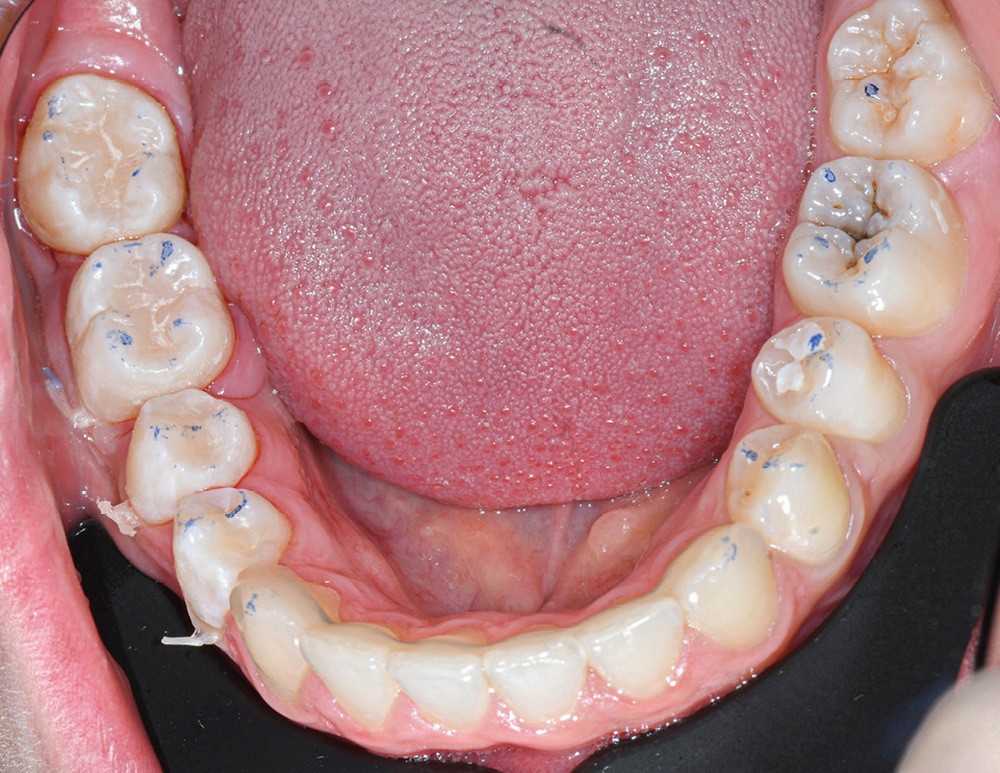

Nous détaillons la technique à travers le cas d’une jeune fille de 18 ans présentant des lésions carieuses sur quatre dents (fig. 1 à 14).

Cette technique de tampon occlusal est indiquée lorsque la face occlusale de la dent à reconstruire est fonctionnelle. Elle évite les multiples incréments occlusaux de résine composite. En contrepartie, elle demande un peu d’entraînement, notamment pour bien replacer le tampon et doser correctement la quantité de résine composite à appliquer avant de tamponner la face occlusale. Néanmoins, une fois maîtrisée, elle est rapide et offre une grande reproductibilité de la situation occlusale de départ en s’évitant les potentielles retouches fastidieuses de fin de séance.